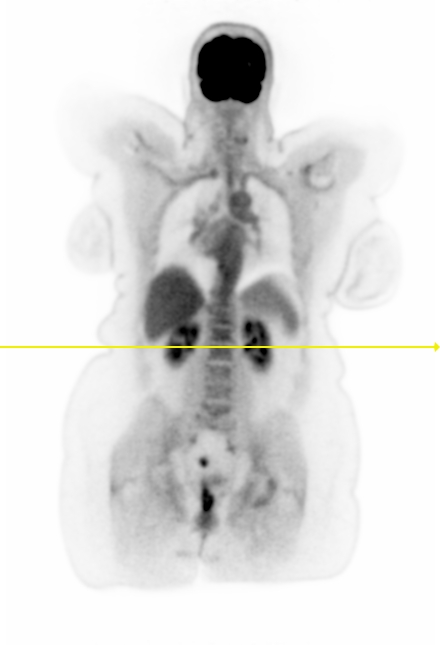

Figure 7 shows three clinical \acFDG dataset examples. The \acDLSE-corrected images are visually very similar to the \acSSS-corrected images. Examining the profile lines in the first row, which displays a breast lesion in a female patient, reveals similar patterns to those observed in the simulated images in Figure 4, with lower activity in the region between the lungs using \acSSS compared to \acDLSE. However, the activities within the lesion are very similar for both \acDLSE and \acSSS.

In the second row dataset, \acDLSE provides better contrast on the nodules than \acSSS, showing similar activity levels between the nodules but with a higher activity peak.

The last dataset shows kidney structures in a large morphology patient (98 kg). The \acSSS-corrected image exhibits an overall higher activity than the \acDLSE-corrected image. After manual segmentation of the kidneys and automatic segmentation of its structures using the FLAB algorithm [37], the contrast is found to be slightly higher in the \acDLSE corrected \acPET images. The contrast is 2.3 with \acDLSE correction, compared to 2.2 with \acSSS correction and 1.8 in the uncorrected image.

| No correction | DLSE | SSS | Profiles |

![]() |

| Sex | Weight | Dose | Coincidences | |

| 1st row | Female | 52 kgs | 160 MBq | 3.0 billions |

| 2nd row | Male | 80 kgs | 244 MBq | 4.7 billions |

| 3rd row | Female | 98 kgs | 297 MBq | 3.8 billions |

The study conducted on clinical \acFDG acquisitions demonstrated consistent results for \acDLSE, producing visually comparable outcomes to \acSSS-corrected images (Figure 7). The method appeared to be robust against significant variations in patient morphology, with weights ranging from 52 to 98 kg. In two of the three cases, \acDLSE-corrected images exhibited slightly higher activity levels, while the \acSSS method showed higher activity in the large morphology patient. This discrepancy may be attributed to inaccuracies in the tail-fitting algorithm used to estimate the scaling factor for multiple scatters, as the tails could potentially be too small for larger morphology patients. In all three examples, the lesion contrasts were found to be greater than those obtained with the \acSSS-based scatter correction.